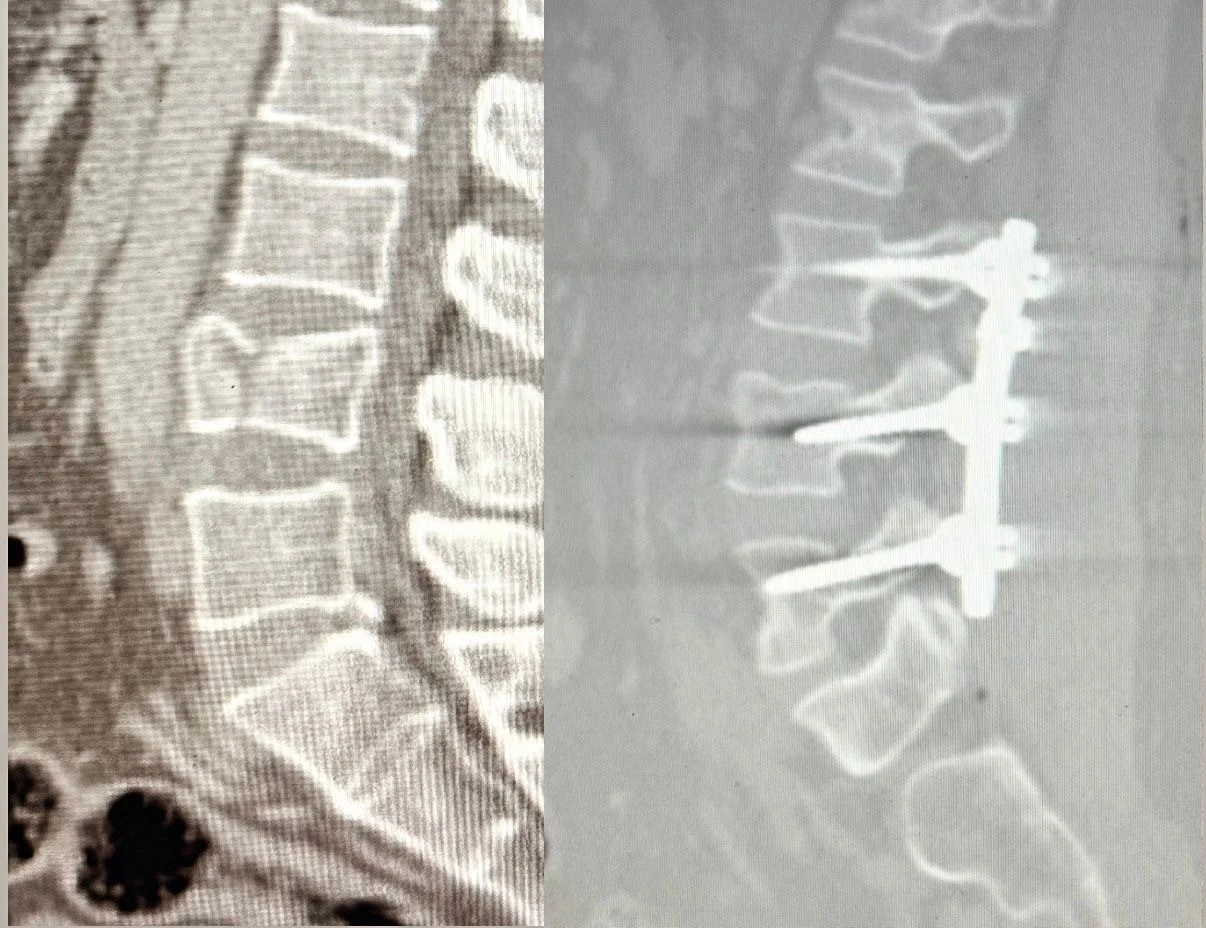

Ağrı’nın Patnos ilçesinde 2,5 metre yüksekten düşen 41 yaşındaki Tekin Maskar, bel bölgesindeki kırık nedeniyle acil servise başvurdu. Yapılan tetkiklerde omurgada çökme kırığı tespit edilmesi üzerine hasta, ortopedi uzmanları Op. Dr. Muhammed Serpi ve Op. Dr. Mustafa İçen tarafından ameliyata alındı.

Ameliyat sırasında bel bölgesindeki omurların sabitlenmesini sağlayan lomber stabilizasyon tekniği kullanıldı. Hastane tarihinde ilk kez gerçekleştirilen bu operasyon sonrası hasta sağlıklı şekilde yürümeye başladı.